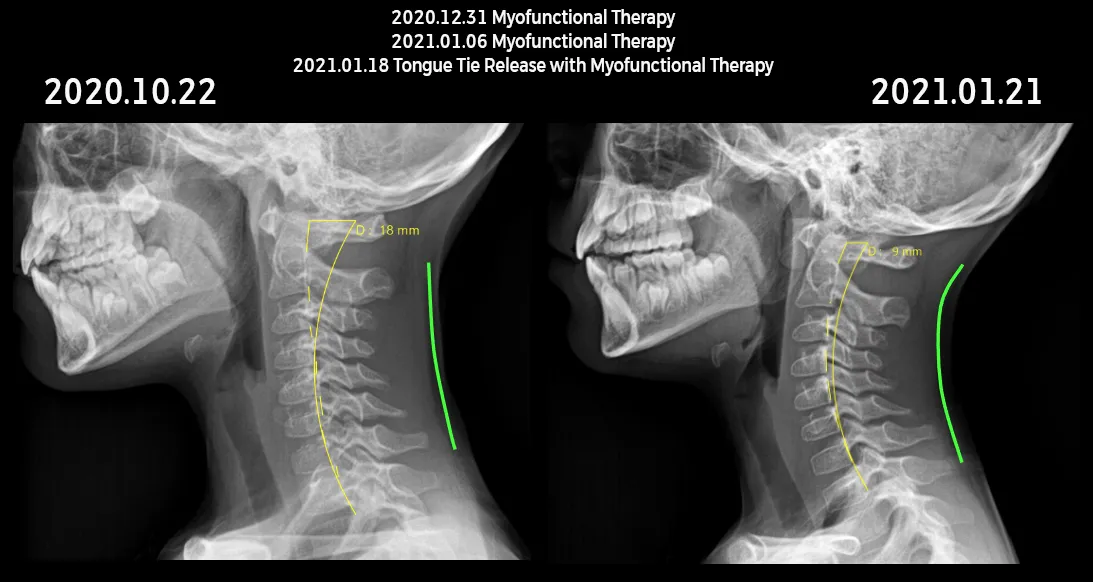

the case of this 9 year old boy who was still a pretty significant toe walker. He was in the hands of a very knowledgeable body worker who, regardless of proper manipulative protocols, was unable to resolve the toe walking. Understanding the deep front line fascial connections, this chiropractor was clever enough to look under the boy’s tongue. What he saw was a suspected tongue tie, so he sent him my way. My evaluation revealed a Grade 3 restriction with compensations at rest and in swallow function. Releasing the tongue tie alone will not fully resolve this boy’s issues- but the appropriate comprehensive care team will! In less than a month, with the proper timing and integration of care, the normal curvature to the cervical vertebrae was restored, diaphragmatic breathing improved, oral balance improved, and the toe-walking completely resolved!

The proper integrative combination of the tongue tie release, the oral myofunctional therapy to retrain the tongue and surrounding muscles from proper balance and function, AND the body work with a bodyworker (osteopath, physical therapist, or chiropractor) to work out compensations further down the line—– all three of these things were essential to this boy’s success.